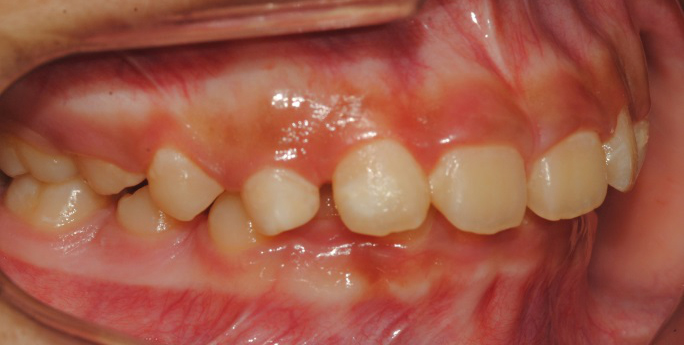

À§ ȯÀÚ´Â À´Ï°¡ ¾Æ·§´Ï¸¦ ³Ê¹« µ¤¾î¿ä(°ú°³±³ÇÕ) ¸¦ ÁÖ¼Ò·Î ³»¿øÇÑ ÃʵîÇлýÀ̾ú½À´Ï´Ù. ÅμºÀå ¾ÇÁ¤ÇüÀåÄ¡ »ç¿ëÈÄ È£ÈíÀÌ °³¼± µÇ¾úÀ¸¸ç Ä¡·áÀü¿¡ ºñÇØ ۰¡ 10cmÁ¤µµ ±Þ¼Ó ¼ºÀåÇÏ¿´½À´Ï´Ù.